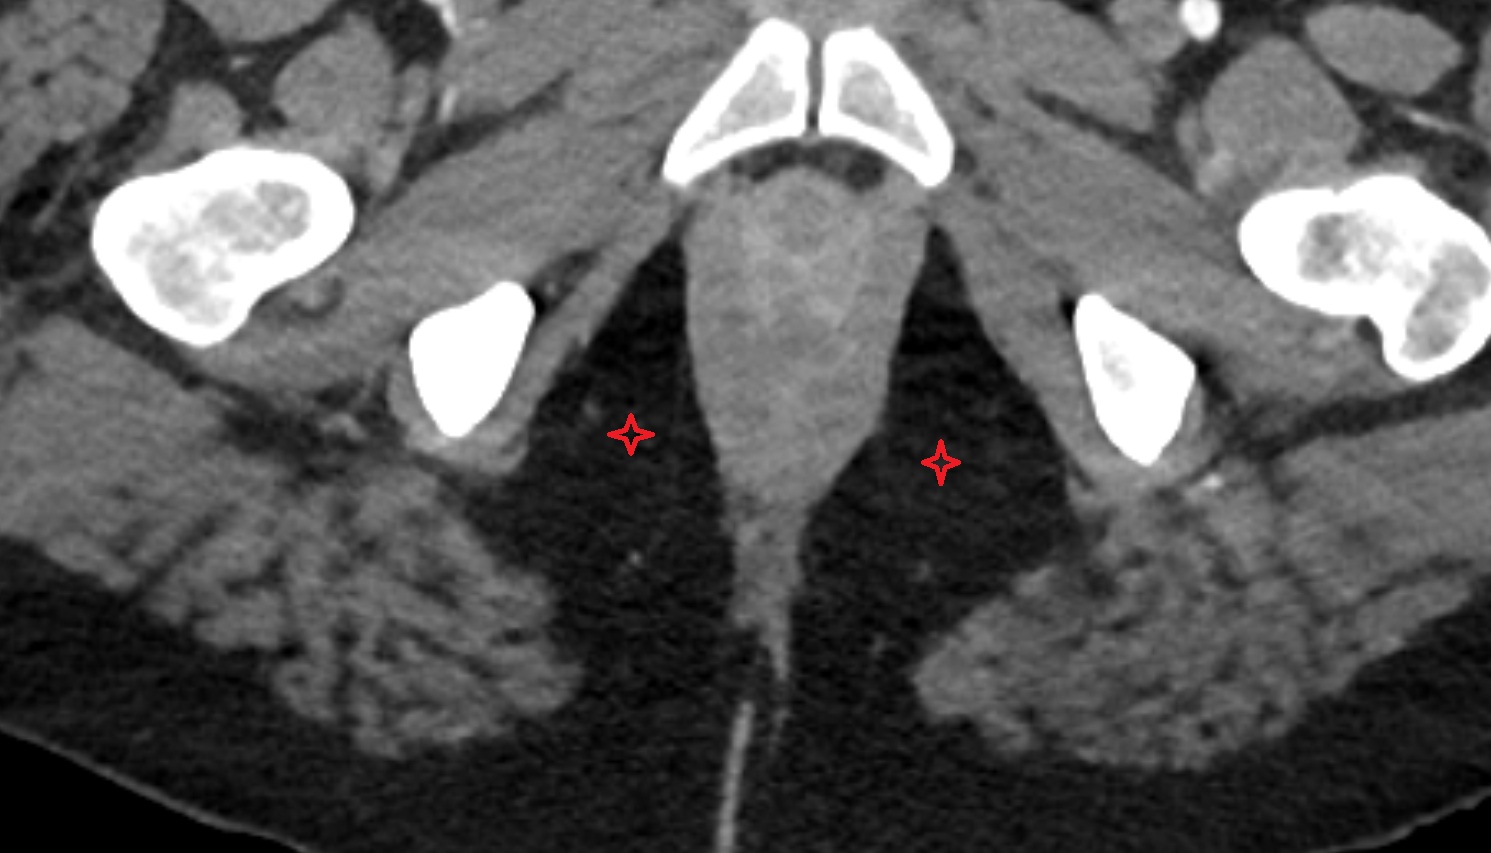

- Corpus cavernosum

- Corpus spongiosum

- Bulb of Penis

- Crus of penis